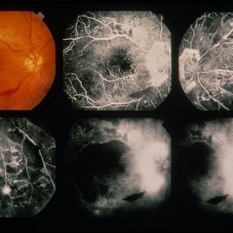

PDR

Jan 24 2014 by Howard Schatz, MD

63-year-old female. Right eye 20/25 and left eye 20/125.